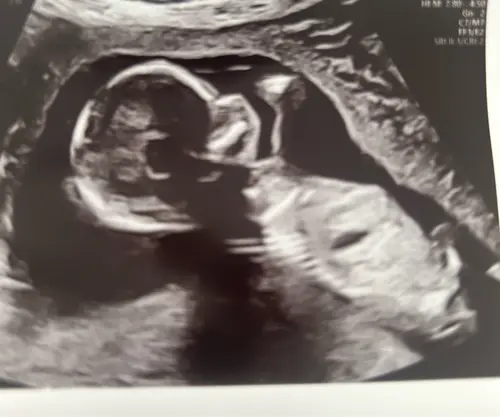

Iemand ??

Op basis van de skull een jongen 馃挋

Jongen denk, maar met deze theorie blijft het een grote gok. Nub is betrouwbaarder als je wat verder bent

Als ik de echo vergelijk met die van mijn zoontje zeg ik jongen 馃┑

Het lijkt wel op dit moment jongen maar is nog vroeg en kan veranderen